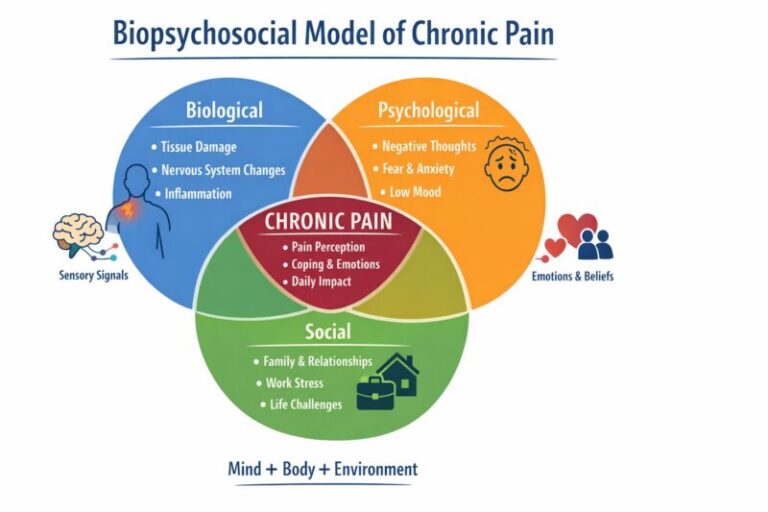

Ban đầu bệnh nhân có thể không có triệu chứng. Dần dần, bệnh nhân thường khai đau ở khớp háng và có thể lan xuống vùng bẹn và/hoặc đùi. Đau thường tăng lên khi thực hiện các hoạt động như đi bộ, leo cầu thang và giảm bớt khi nghỉ ngơi. Bệnh nhân vẫn có cảm giác đau, ngay cả khi không cử động.

Điều trị hoại tử vô mạch chỏm xương đùi thay đổi từ bảo tồn đến xâm lấn, phụ thuộc vào nhiều yếu tố, và mỗi bệnh nhân cần được đánh giá riêng biệt để xác định giải pháp tối ưu. Các yếu tố cần xem xét bao gồm tuổi của bệnh nhân, mức độ đau/khó chịu, vị trí và mức độ hoại tử, các bệnh kèm và đặc biệt là mặt khớp có bị xẹp xuống hay không. Các phương pháp điều trị được thực hiện tốt nhất ở giai đoạn trước khi mặt khớp bị xẹp và bao gồm cả các lựa chọn phẫu thuật cũng như không phẫu thuật. Nếu không được điều trị, hoại tử chỏm xương đùi có thể dẫn đến gãy xương dưới sụn chỉ trong vòng 2 đến 3 năm.

Các phương pháp bao gồm vật lý trị liệu, hạn chế mang vật nặng, cai rượu, ngừng điều trị bằng corticoid, thuốc giảm đau và một số loại thuốc nhắm mục tiêu.

Các mục tiêu/biện pháp của phục hồi chức năng trong hoại tử vô khuẩn chỏm xương đùi bao gồm:

- Giáo dục: Về phòng ngừa, loại bỏ hoặc giảm thiểu các yếu tố nguy cơ như hút thuốc lá, uống rượu bia quá mức, béo phì và corticosteroid